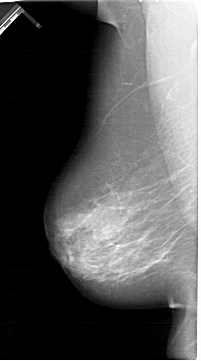

A_1390_1.LEFT_MLO

LEFT_MLO LINES 6481 PIXELS_PER_LINE 3601 BITS_PER_PIXEL 12 RESOLUTION 43.5 NON_OVERLAY